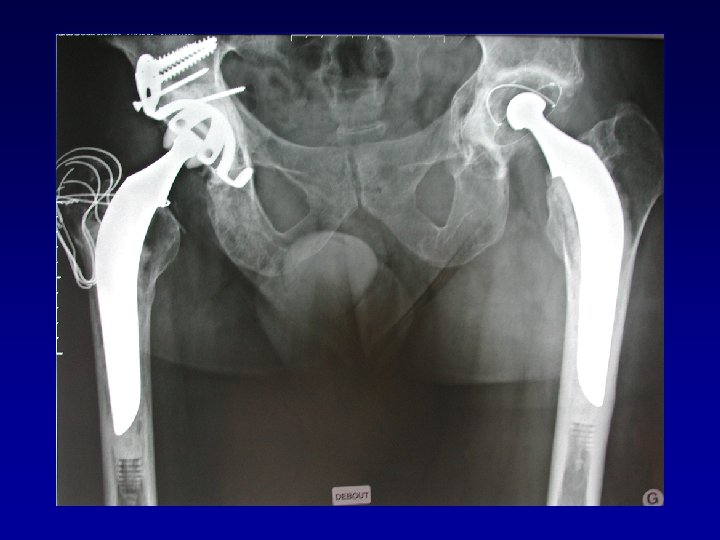

Arthroplastie totale de hanche sur fracture du cotyle complexe (LCH) • Voie d’abord par

Arthroplastie totale de hanche sur fracture du cotyle complexe (LCH) • Voie d’abord par TROCHANTEROTOMIE Libération de la fibrose, capsule, cicatrices • Permet : Exposition Récupération de la longueur Mobilité

Arthroplastie totale de hanche sur fracture du cotyle complexe Recentrage, reconstruction, orientation du cotyle

Arthroplastie totale de hanche sur fracture du cotyle complexe Recentrage, reconstruction, orientation du cotyle • • Greffe Ostéosynthèse par plaque MK Surtout si pseudarthrose Réduction de la luxation